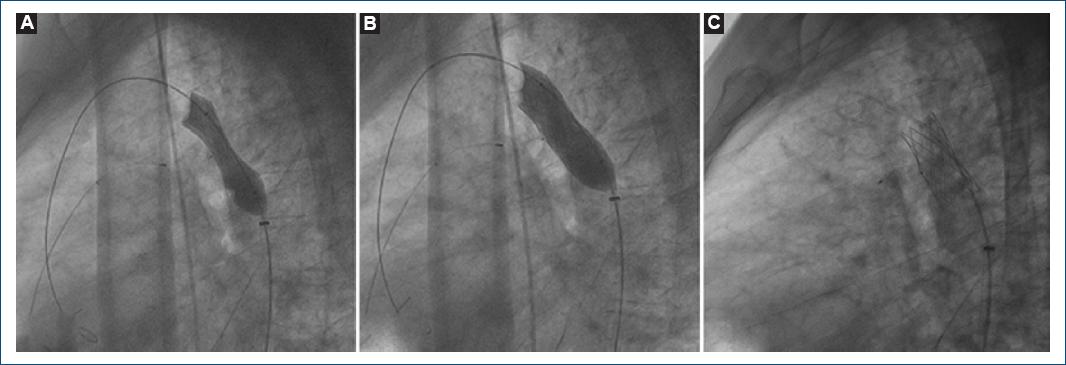

Se decidió utilizar un dispositivo Amplatzer de 6 × 6 mm para realizar la prueba de oclusión del conducto, registrando un descenso de las cifras pulmonares sistólica, diastólica y media a 46, 21 y 29 mmHg, respectivamente (ratio Pp/Ps < 0.5) y 6 unidades Wood. El paciente se mantuvo asintomático, por lo cual se liberó el dispositivo. Para la coartación, al poseer adecuada anatomía y sin evidencia de aneurismas, se decidió realizar aortoplastia con stent metálico PALMAZ 40 mm (Fig. 2). El ecocardiograma de control reportó cierre del conducto sin shunt residual y con función sistólica del ventrículo derecho conservada, TAPSE 17 mmHg y onda S de 10 cm/s, además de corroborar la estenosis aórtica moderada con un área valvular de 0.9 cm2/m2, gradiente medio de 36 mmHg y Vmax de 3.75 m/s. El gradiente medio de la aorta descendente era 8.3 mmHg. El paciente fue egresado por mejoría. Se evaluarán el comportamiento hemodinámico y las resistencias pulmonares, y se hará seguimiento de la estenosis aórtica moderada.